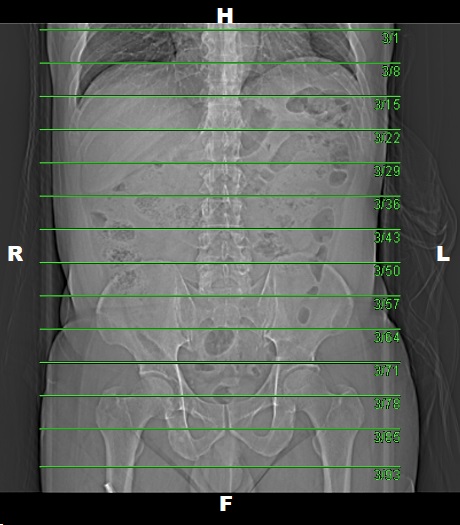

Venous Phase

• Plan the Scan FOV (SFOV) box at topogram image.

• Set the top line at the level upper diaphragm.

• Set the bottom line at the level inferior ischial ramus.

• Ensure the lateral line to cover patient’s body outline.

• Remind the patient before scanning as the breathing instruction will be given.

• Delay: 25 seconds (after Liver LAP).

Delayed 5 Minutes (Optional)

• Liver

• Plan the Scan FOV (SFOV) box at topogram image

• Set the top line at the level of above diaphragm.

• Set the bottom line at the level of end of liver.

• Full abdomen

• Set the bottom line at the level of inferior ischial ramus.

Multiplanar Reconstruction (MPR)

Coronal LAP IV

• Image Thickness: 3.0 mm

• Number of Image: 19

• Coverage: Anterior to Posterior of abdomen

Coronal PVP IV